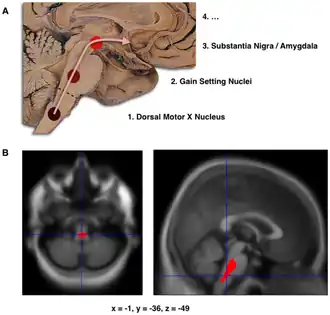

B. Lokalisering van het gebied waar een significante afname in hersenvolume zichtbaar is in beginnende Parkinson, vergeleken met een groep deelnemers die géén Parkinson hadden. Schade aan de hersenstam bleek bij deze studie mogelijk het eerste waarneembare stadium van neuropathologie bij de ziekte van Parkinson.[1]

De stadiëring van de ziekte van Parkinson werd voor het eerst beschreven door Heiko Braak in 2003.[4] Braak en zijn collega's stellen dat Parkinson begint wanneer een aanvaller van buitenaf het lichaam binnendringt via de neus of het gastro-intestinale systeem en het centrale zenuwstelsel (CZS) bereikt. De aanwezigheid van lewy-lichaampjes in het enterische en perifere zenuwstelsel onderbouwen deze stelling. De lewy-pathologie verspreidt zich door het CZS en raakt vooral dikke en grotendeels ongemyeliniseerde neuronen. Volgens Braak en collega's begint de ziekte in het enterische zenuwstelsel en treedt het het CZS binnen via de nervus vagus.[5]